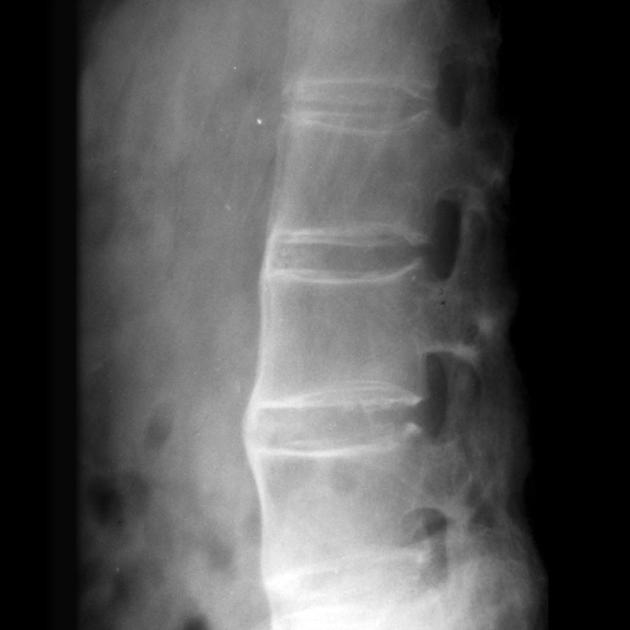

强直性脊柱炎的诊断方法与标准

说起强直性脊柱炎的诊断,就像是破解一个复杂的医学密码。 这个"密码"不仅需要医生的专业知识,还需要患者的积极配合。 可能很多人会问:"为什么诊断这个病这么复...